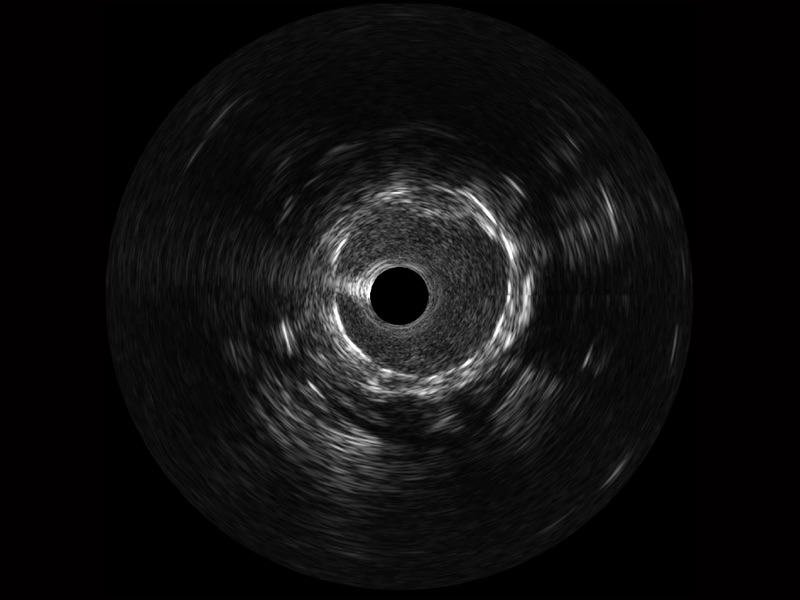

• 传统IVUS图像

对比传统IVUS导管成像,亚星官网宽频IVUS图像的近场支架梁显影更细腻,远场中膜外血管仍清晰可辨,兼顾远中近,兼顾分辨力与穿透深度